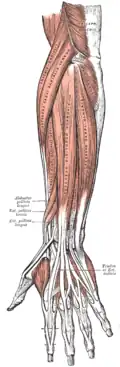

Die Muskeln des Unterarmes werden ihrer Lage nach in zwei Gruppen unterteilt: Die Muskeln, die am lose hängenden Arm innen liegen und somit den Arm anbeugen (Flexoren) und die Muskeln, die außen liegen und den Arm strecken (Extensoren). Diese beiden Gruppen bestehen jeweils aus zwei einzelnen Schichten, die von der Körperoberfläche in die Tiefe gehen.

| Musculus flexor carpi radialis | Musculus pronator quadratus | Musculus brachioradialis | Musculus extensor carpi ulnaris | Musculus abductor pollicis longus |

| Musculus flexor carpi ulnaris | Musculus flexor pollicis longus | Musculus extensor carpi radialis brevis | Musculus extensor digitorum | Musculus extensor pollicis brevis |

| Musculus flexor digitorum superficialis | Musculus flexor digitorum profundus | Musculus extensor carpi radialis longus | Musculus extensor digiti minimi | Musculus extensor pollicis longus |

| Musculus palmaris longus | Musculus extensor indicis | |||

| Musculus pronator teres | Musculus supinator | |||